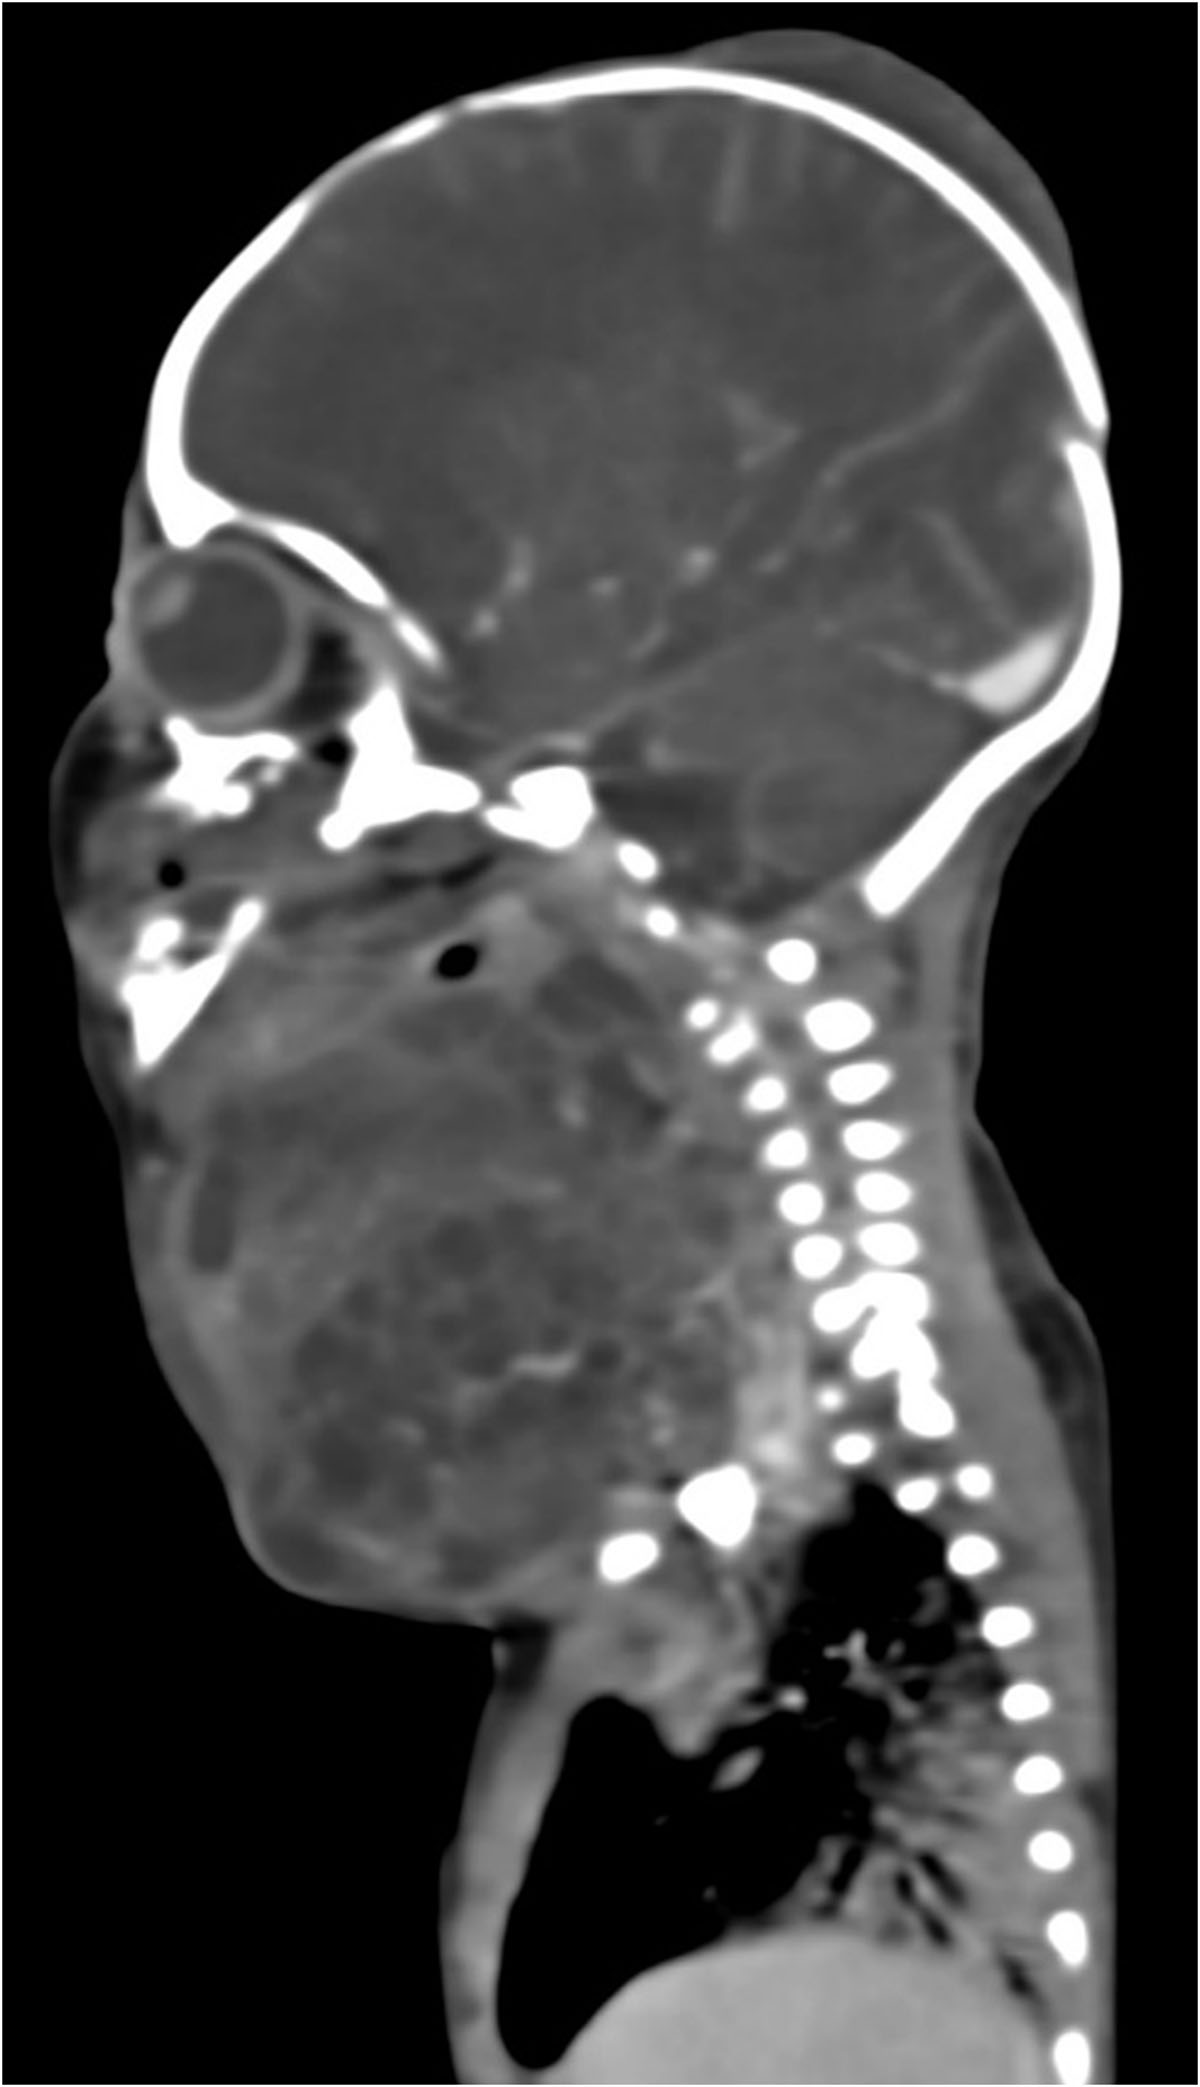

Paciente femenina recién nacido producto de primer gesta sin antecedentes heredofamiliares de relevancia con adecuado control prenatal; cuenta con antecedente patológico de amniodrenaje en la semana 34.4 por polihidramnios. Obtenida por vía abdominal, con manejo de vía aérea avanzada, por presentar tumoración en la región cervical derechade aproximadamente 12×8 cm, indurada, de bordes irregulares.

Se identifica imagen redondeada, de bordes lobulados, dependiente de tejidos blandos, heterogénea por áreas sólidas y quísticas internas, así como algunas calcificaciones irregulares dispersas, tras la aplicación de medio de contraste con realce ávido heterogéneo en sus porciones sólidas, con dimensiones de 89.3×88.3×80.9 mm y volumen de 333.6 cc; localizada en los espacios masticador, parotídeo, parafaríngeo, submandibular, visceral, supraesternal, perivertebral bucal y cervical posterior derechos.5. IMÁGENES

El teratoma cervical es una neoplasia congénita rara, derivada de células germinales pluripotenciales que contienen tejidos de las tres capas embrionarias. Representa menos del 5% de los teratomas pediátricos y su localización en el cuello puede ocasionar compromiso de la vía aérea, constituyendo una urgencia neonatal potencialmente mortal.

La tomografía computarizada (TC) muestra una masa compleja bien delimitada, con componentes sólidos, quísticos, calcificados y grasos, hallazgo característico de los teratomas maduros. La TC permite valorar la relación con estructuras vasculares, la vía aérea y el mediastino, siendo útil en la planificación quirúrgica.

La resonancia magnética (RM) constituye la técnica de elección para la evaluación anatómica detallada, debido a su superior contraste tisular y la ausencia de radiación ionizante. En secuencias ponderadas en T1 se observan focos hiperintensos por grasa o hemorragia, mientras que en T2 predominan las áreas quísticas hiperintensas [1,5]. Además, la RM define la extensión hacia el mediastino o la base del cráneo y permite valorar el desplazamiento o compresión traqueal, aspectos críticos para el manejo perinatal.

El tratamiento consiste en la resección quirúrgica completa, la cual puede requerir abordajes multidisciplinarios, especialmente cuando existe compromiso de la vía aérea. En casos diagnosticados prenatalmente, se recomienda la planificación del parto mediante la técnica EXIT (Ex UteroIntrapartumTreatment), que permite asegurar la ventilación del recién nacido antes de cortar el cordón umbilical [1,3].